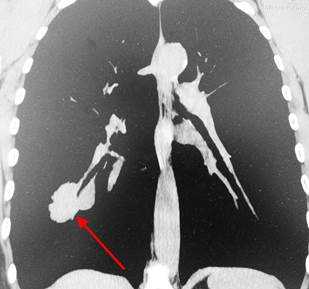

Метастазы в легких на КТ

Гематогенные метастатические узлы в легких на КТ имеют довольно четко очерченные и ровные контуры. Нечеткие, расплывчатые или лучистые контуры наблюдаются в том случае, если есть инвазивный рост в окружающую легочную ткань. Локализуются преимущественно в нижних, периферических отделах легких, хаотично, без очевидной связи с бронхами и крупными легочными сосудами.

Вторичные узлы гематогенного характера чаще всего имеют ровные края, четкие контуры и однородную структуру. Возможны изменения структуры опухоли вследствие кровоизлияния в паренхиму, обызвествлений, некроза центральной части узла, а также рубцов. Края узла могут стать нечеткими, расплывчатыми, если опухоль провоцирует отек легочной паренхимы, либо «лучистыми», если имеет место опухолевый лимфангиит.

Чаще всего метастазы выглядят как множественные очаги. Одиночные вторичные узлы крайне редки и встречаются меньше чем в 5% случаев. Чем больше узлов выявлено, тем выше вероятность их метастатической природы. Одиночный метастаз нужно дифференцировать с первичным раком, для этого обычно требуется тканевое исследование после оперативного вмешательства или биопсии.

Гематогенные метастазы наиболее часто локализуются в периферических отделах легких, вдали от крупных сосудисто-бронхиальных пучков, вблизи плевральной оболочки. При множественных поражениях гематогенного характера наблюдается тенденция к увеличению количества очагов в направлении «сверху-вниз». Чаще гематогенные метастазы расположены хаотично, вне четкой связи с бронхами и видимыми легочными сосудами. Практически не бывает такого, чтобы гематогенные вторичные узлы находились только с одной стороны, или занимали только одну долю или сегмент. При наличии такого распределения в первую очередь нужно думать о туберкулезе (верхние доли), множественных абсцессах и т. д.